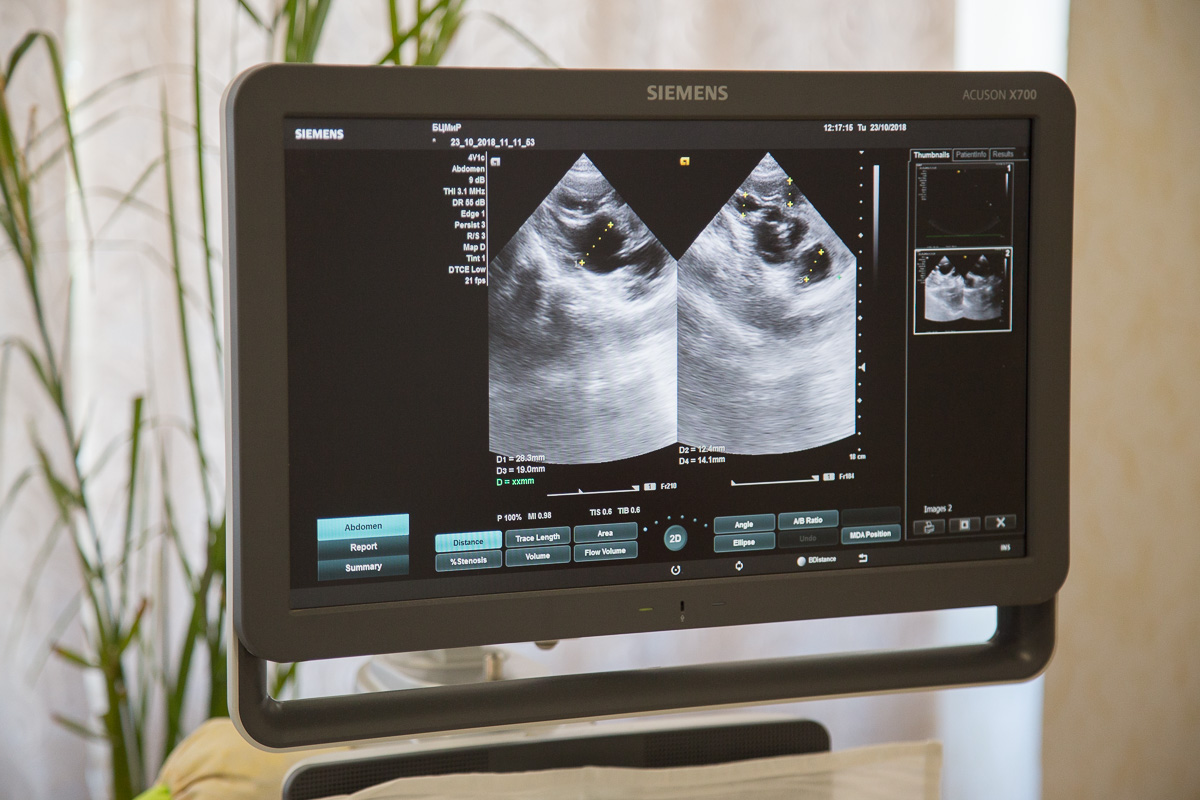

Новые возможности дал и современный аппарат УЗИ.

«На экране – изображение снимка маленького пациента. Он находится на стационарном учёте, ему 5 лет, и у него врождённая патология почек. Ребёнок был прооперирован 3 года назад, сейчас находится под наблюдением. Этот аппарат УЗИ проводит множество исследований – головного мозга, сосудов головы и шеи, щитовидной железы, лимфатических узлов, сердечно-сосудистой, мочевыделительной систем, опорно-двигательного аппарата», – рассказал заведующий отделением функциональной диагностики Афанасий Добростомат.